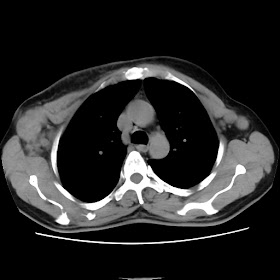

A 62 years old man with enlarged mole on chest since 2 months.

CT chest :-